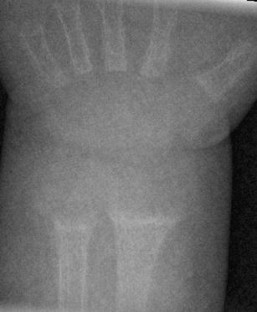

Fig. 1

Fig. 2